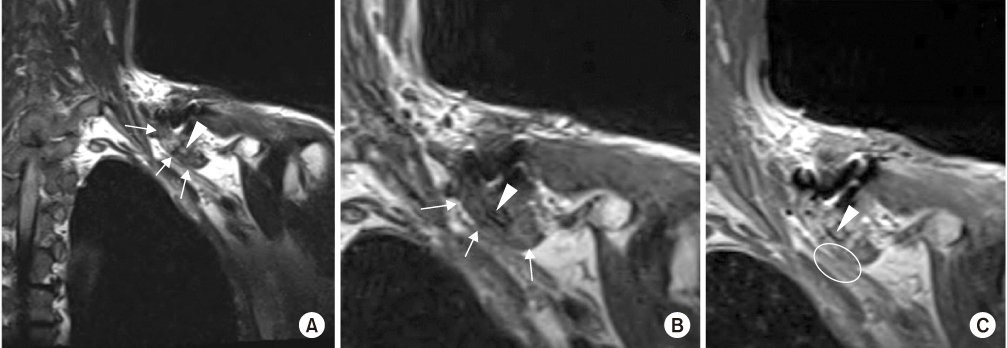

Fig. 3

Fibrotic mass lesion margin (white arrows) around the small bony fragment (white arrowheads) inferior to the clavicle, which compressed the adjacent brachial plexus and caused signal changes within the brachial plexus (white circle) on the (A) cervical spine T2 coronal image, (B) cervical spine T1 coronal image, and (C) cervical spine T1 enhanced coronal image.